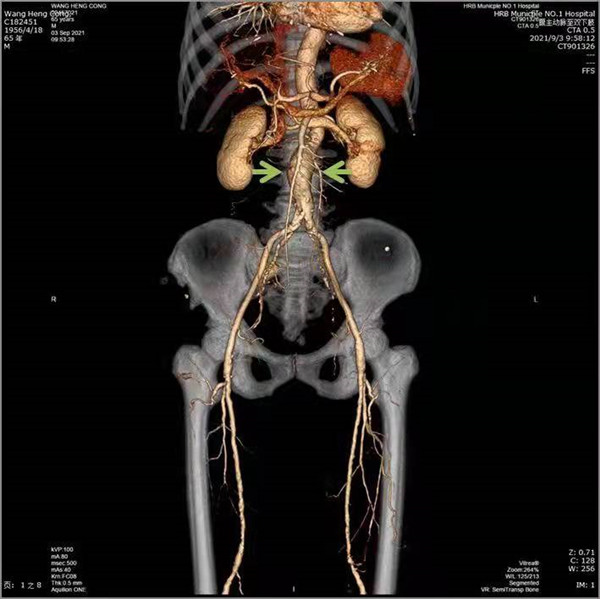

近日,家住哈市的王大爺遇到了煩心事,肚子總是漲漲的,雖然不疼但總是不舒服,一吃點東西會更加嚴重。本以為是消化不良,過幾天自然就緩解了,不成想這一過就是一個多月,症狀不但沒有緩解,反而越來越重,這才引起了重視。更鬧心的是看了好幾家醫院,檢查沒少做卻找不到原因。最終慕名前往哈爾濱市第一醫院就診,經過普外三科周偉忠主任醫療團隊的仔細診查,原來是得了「腹主動脈瘤合併腸繫膜上動脈狹窄」。

術前

據普外三科(乳腺、血管外科)周偉忠主任介紹:腹主動脈瘤(AAA)是指腹主動脈呈瘤樣擴張,好發於老年男性,尤其是吸煙者,最常見的病因是動脈粥樣硬化。多數患者無症狀,多在體檢時偶然發現,所以早期的篩查非常重要。該病平時沒有症狀,但是一旦出現症狀(如突發腰腹痛等)往往提示動脈瘤即將破裂或已經出現破裂。有些患者以動脈瘤破裂、失血性休克為最初表現,因此,臨床上常稱之為「體內定時炸彈」。 同時腹主動脈瘤會形成附壁血栓,這種血栓也存在有脫落風險,可能會導致遠端動脈的栓塞,引起下肢壞死,造成嚴重後果。

腸繫膜上動脈狹窄臨床發病率低、發病隱匿、症狀不典型,常和其他腹部疾病混淆。臨床醫生對這種疾病的認識不足導致慢性腸繫膜缺血患者的診斷延誤、診斷不足和治療不足,可能造成致命的急性腸繫膜缺血而死亡。本例患者是以腸繫膜動脈缺血症狀就診,同時發現了腹主動脈瘤,這種情況很少見。

由於患者高齡、基礎疾病較多,如同時行兩種手術,存在較高風險,但病人強烈希望能夠一起解決這兩個問題,經全面評估考慮,周偉忠主任決定兩種疾病同時處理,行微創腔內治療。術前詳細測定患者病變段血管數據,制定了周詳的手術方案,在周偉忠主任帶領下,瞿鵬、劉焱喆醫生及麻醉醫生、導管室配合下實施手術。藝高人膽大,術中,周偉忠主任團隊於主動脈放置覆膜支架隔絕腹主動脈瘤,腸繫膜上動脈支架植入使腸繫膜上動脈血流恢復。手術順利完成。術後患者恢復良好,術後三天即下地活動,患者腹痛、腹脹症狀消失,一周後出院。